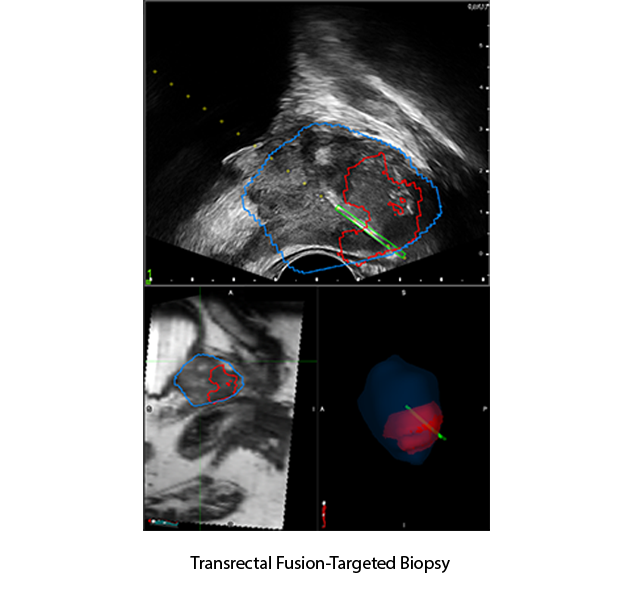

TRANSRECTAL

SIDEFIRE/ENDFIRE

Unique Triplane Transducer and High-Resolution Endfire Transducer with navigation sensors

- Integrated into a familiar, efficient transrectal biopsy workflow

- Freehand biopsy procedure compatible with sidefire or endfire transducer

Requires electromagnetic (EM) tracking